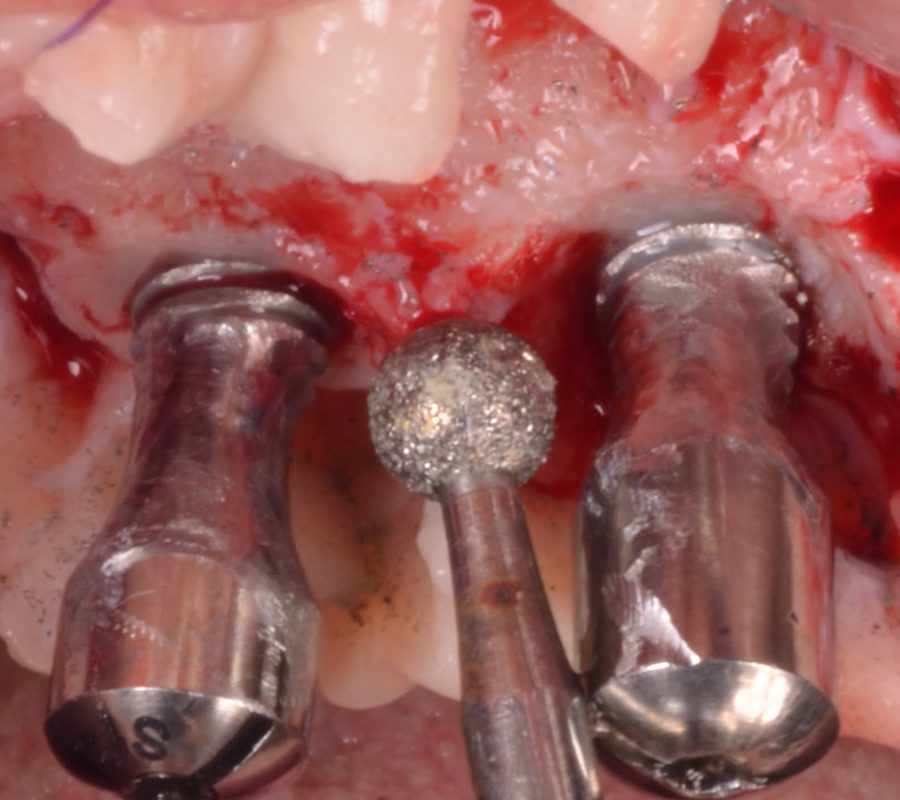

• Delve into surgical techniques for peri-implantitis management, including resective, reconstructive, combined therapy, and soft tissue conditioning.

5. Develop proficiency in surgical techniques for peri-implantitis management, including resective, reconstructive, combined therapy, and soft tissue conditioning.

The hands-on practice session, comprising five hours, will focus on surgical therapy in peri-implantitis management using the art of state models. Participants will have the opportunity to apply their theoretical knowledge in a practical setting, further refining their skills and confidence in treating peri-implantitis.